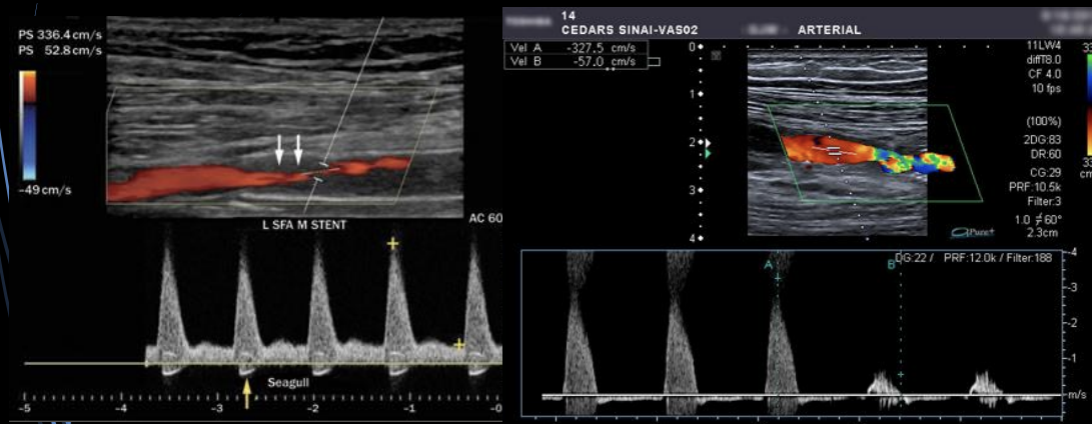

6

A

Cambios en la onda

Estenosis vascular